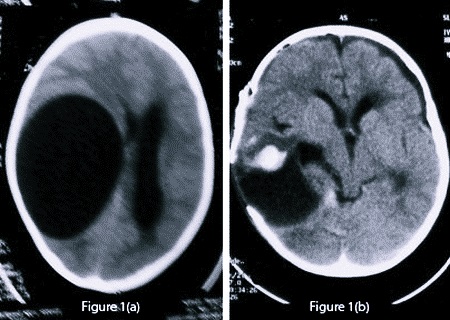

Маленькие по размеру образования обычно отличаются субклиническим течением и поэтому их выявляют совершенно случайно путем нейровизуализирующего обследования головы. Если же киста имеет достаточно большие объемы, то из-за ограниченного интракраниального пространства она может стать причиной развития внутричерепной гипертензии, впоследствии чего произойдет сильное сдавливание соседних мозговых структур.

На сегодняшний день основными методами диагностики и последующего прогноза данной болезни являются МРТ (магнитно-резонансная томография) и КТ. Полученная томограмма показывает состояние всех составляющих мозга (эпифиза, мозжечка, гипофиза, нервных ганглий и других частей). С ее помощью можно увидеть место расположения перивентрикулярного глиозного очага и атрофических рубцовых следов внутри головного мозга без вскрытия черепной коробки, оценить их форму, размеры и интраселлярный рост.

Кроме того, данные способы обследования позволяют сделать дифференциальную диагностику промежуточного состояния между доброкачественной кистой и злокачественной опухолью. После внутривенного введения специального контрастного вещества его продукт накапливается в опухолевых тканях, а киста при этом не становится контрастной.

Если киста постепенно увеличивается в размерах, оказывая повышенное давление на соседние части головного мозга, то не следует ждать, пока она рассосется самостоятельно. Подобный случай, как и заметное ухудшение самочувствия пациента, является показанием к хирургическому вмешательству и проведению операции с помощью лазера. Данная процедура позволяет полностью избавиться от полости, наполненной жидкостью.